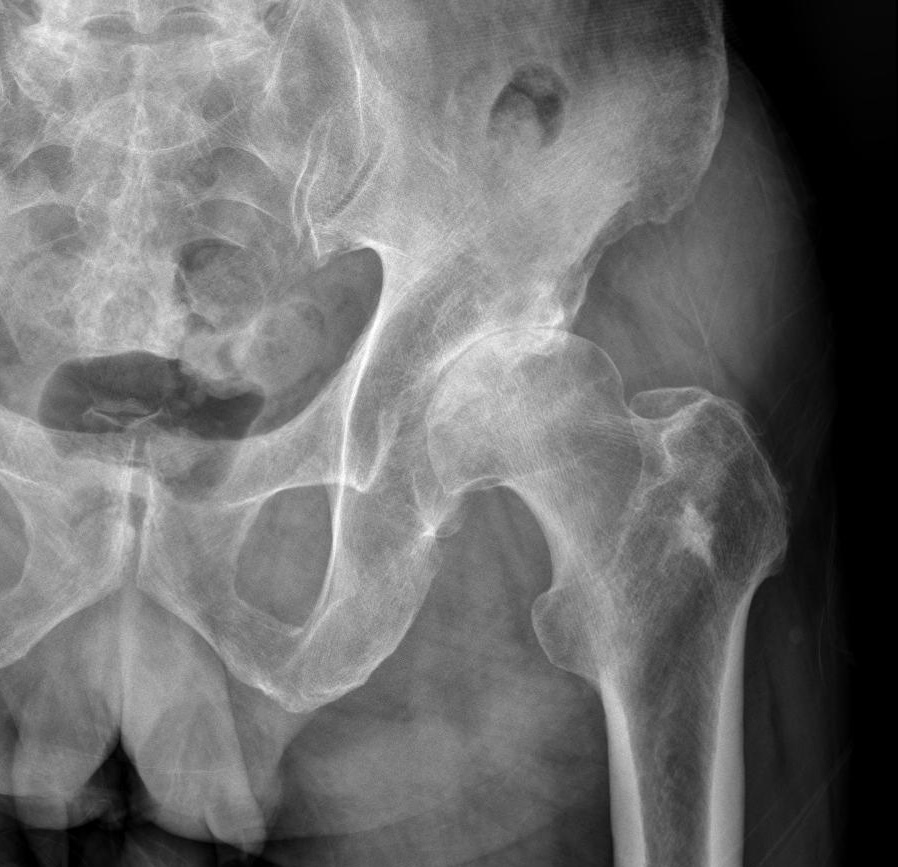

영상 진단

X-ray: 고관절의 연골 마모, 뼈의 변형 및 관절 공간의 감소 등을 확인할 수 있습니다.

MRI: 연골, 인대, 그리고 뼈의 상세한 이미지를 제공합니다. MRI는 초기 단계의 골관절염 진단에 유용할 수 있습니다.

Q: 고관절 골관절염 진단을 위해 가장 중요한 검사는 무엇인가요?

A: X-ray 검사가 가장 중요하며, 이를 통해 관절의 손상과 연골 마모 정도를 확인할 수 있습니다. 필요에 따라 MRI 검사가 추가적으로 수행될 수 있습니다.